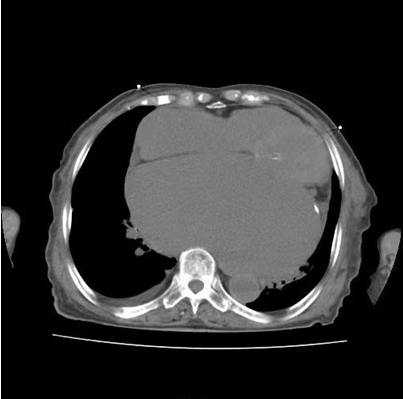

图二:患者胸CT所示巨大左心房

患者因“发作性气短20余年”之主诉入院,多次心脏超声诊断为风湿性心脏瓣膜病二尖瓣狭窄,此次因症状再发加重入院。经评估患者二尖瓣瓣口面积为0.67cm2,二尖瓣跨瓣压差为22mmHg,左房前后径94mm,左右径109mm,为重度风湿性二尖瓣狭窄伴罕见巨大左心房。在心内二科主任寿锡凌带领下,全科室充分讨论。因患者年龄大、基础情况差、无法耐受外科手术治疗,药物治疗不能解除瓣膜狭窄,只能选择经皮二尖瓣球囊扩张成形术。但鉴于患者巨大左心房已使心脏结构发生了巨大变化,单纯通过传统DSA影像结合经胸心脏超声指引下穿刺房间隔引起心脏破裂、心脏填塞、房间隔穿刺部位不佳影响手术操作、二尖瓣狭窄严重难以寻找二尖瓣瓣口、球囊扩张时球囊扩张位置不佳、术中难以即刻评估瓣膜扩张效果等均会导致手术失败进而威胁患者生命。考虑到心腔内超声宛如“心腔内的眼睛”可实时为术者提供心腔内的解剖结构毗邻关系,弥补传统DSA影像结合经胸心脏超声的不足,能为术者决策实时提供指导,确保手术能够安全、准确、顺利完成,最终决定为患者行心腔内超声指引下经皮二尖瓣球囊扩张成形手术。

此例手术由姚晓伟主任医师、韩稳琦主治医师、赵永勇主治医师通过心腔内超声指导下进行,通过心腔内超声精准构建心脏模型、直视下穿刺房间隔,后通过心腔内超声及左心房造影寻找狭窄的二尖瓣瓣口,并指引二尖瓣球囊扩张导管顺利经狭窄的二尖瓣口至左心室,在心腔内超声的指引下选择最佳位置以26mm球囊导管反复扩张狭窄的二尖瓣。术后第二天复查心脏超声,患者二尖瓣瓣口面积由术前0.67cm2扩大到术后1.69cm2,二尖瓣跨瓣压差由术前22mmHg降低至术后的16mmHg,左房前后径由术前94mm减小至术后92mm,左房左右径由术前109mm减小至术后102mm,并且球囊扩张后未引起明显的二尖瓣反流,患者心功能明显改善,自觉症状明显好转出院。